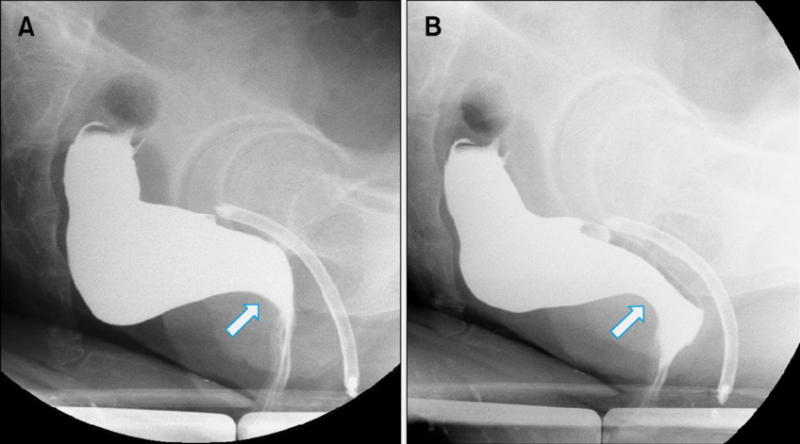

3. Дефекография — либо с помощью рентгена, либо с помощью МРТ. Пациенту в прямую кишку вводят рентгеноконтрастное вещество, и он пробует сходить в туалет. В это время ему делают МРТ или специальный рентген. Так врач видит, куда идет каловый комок, где он застревает, как продвигается, есть ли в кишке дополнительные карманы, полностью опорожняется кишка или нет.

А здесь есть проблемы с работой лобково-прямокишечной мышцы. Источник: researchgate.net